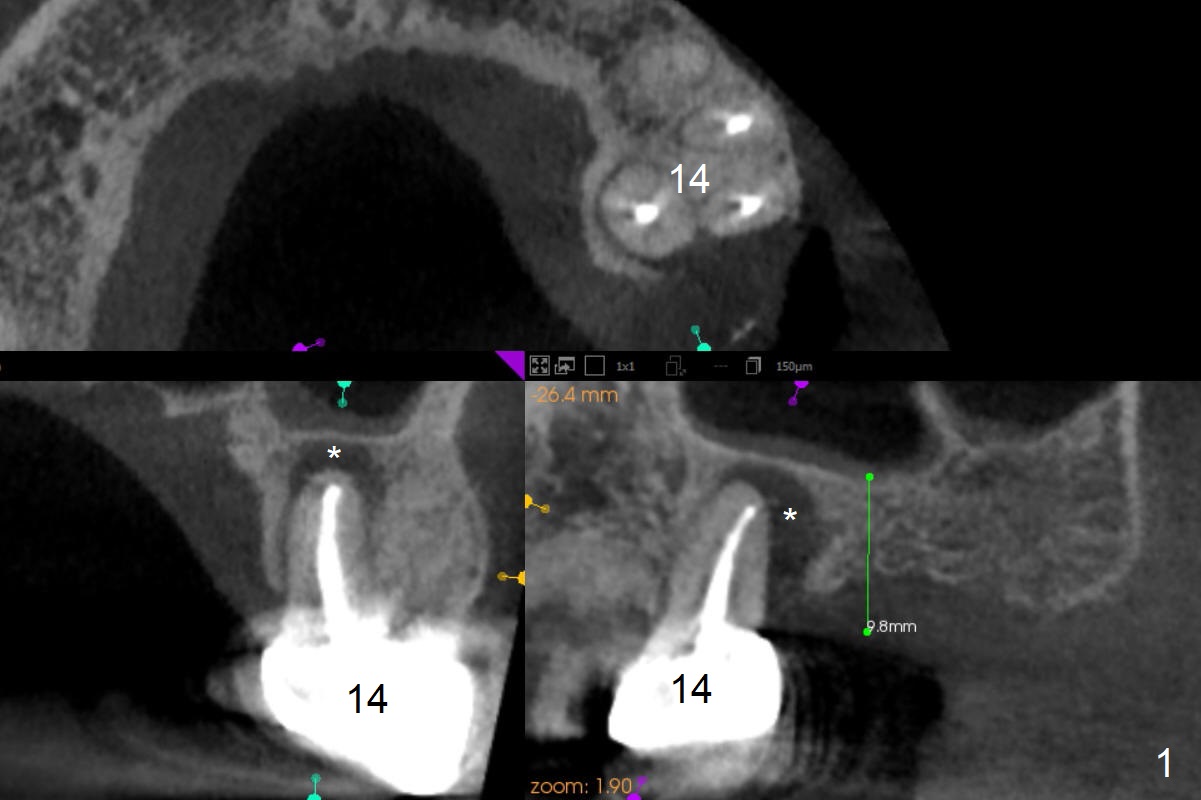

A 53-year-old man cannot chew on the left side with distal abscess in spite of RCT for #14 (* in Fig.1,2 (taken 11 ad 21 months postop, respectively)). After extraction (Fig.3 (CBCT coronal section) black area), start osteotomy with 2 mm drill (red outline) in the septum buccal to the palatal (P) socket). Following 2 mm drill removal (Fig.4), use 4.3 mm Magic Drill (red outline) for ~ 9 mm. When the osteotomy is being done, the osteotomy most likely shifts palatal (Fig.5 arrow) because of thin bone palatally. When the MD is removed (Fig.6), use Magic Sinus Lifter (Fig.7 pink) for sinus lift (arrow). The implant is to be 5x11 mm or larger. Because of the distal defect (Fig.1,2), start osteotomy mesially. Take Alginate impression before surgery for possible orthodontic treatment. Since bone density is high, use higher voltage and longer time for X-ray.